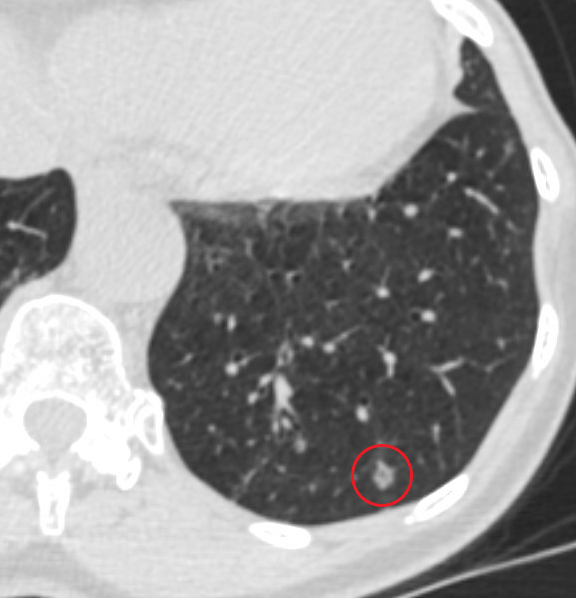

Ramsy Abdelghani, MD@Rabdelgh·

Growing LUL pleural based lesion with no airway leading to it and negative on IR biopsy. Was able to navigate close (within 2cm) to the lesion, biopsy, and adjust using CBCT. Positive for poorly differentiated carcinoma. I would have never tried this without CBCT and Robotics.